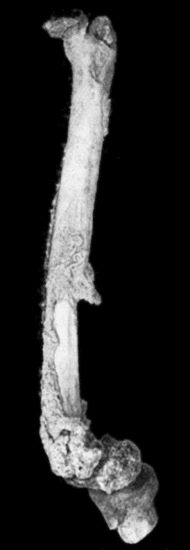

118.Shaft of the Femur after Acute Osteomyelitis 444

119.Femur and Tibia showing results of Acute Osteomyelitis 445

122.Sequestrum of Femur after Amputation 453

123.New Periosteal Bone on Surface of Femur from Amputation Stump 454